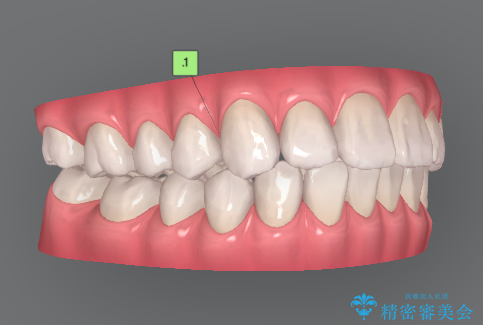

- 前歯の噛み合わせの開きの改善を求めて来院されました。

奥歯はほとんど動かさず(奥歯の噛み合わせはほとんど変えず)前歯のIPR矯正でガタつき前突感(出っ歯感)の改善を計画します。

ほとんど前歯のみの矯正治療であることからトータル14枚のマウスピースで並べるインビザラインライトによる治療を行います。